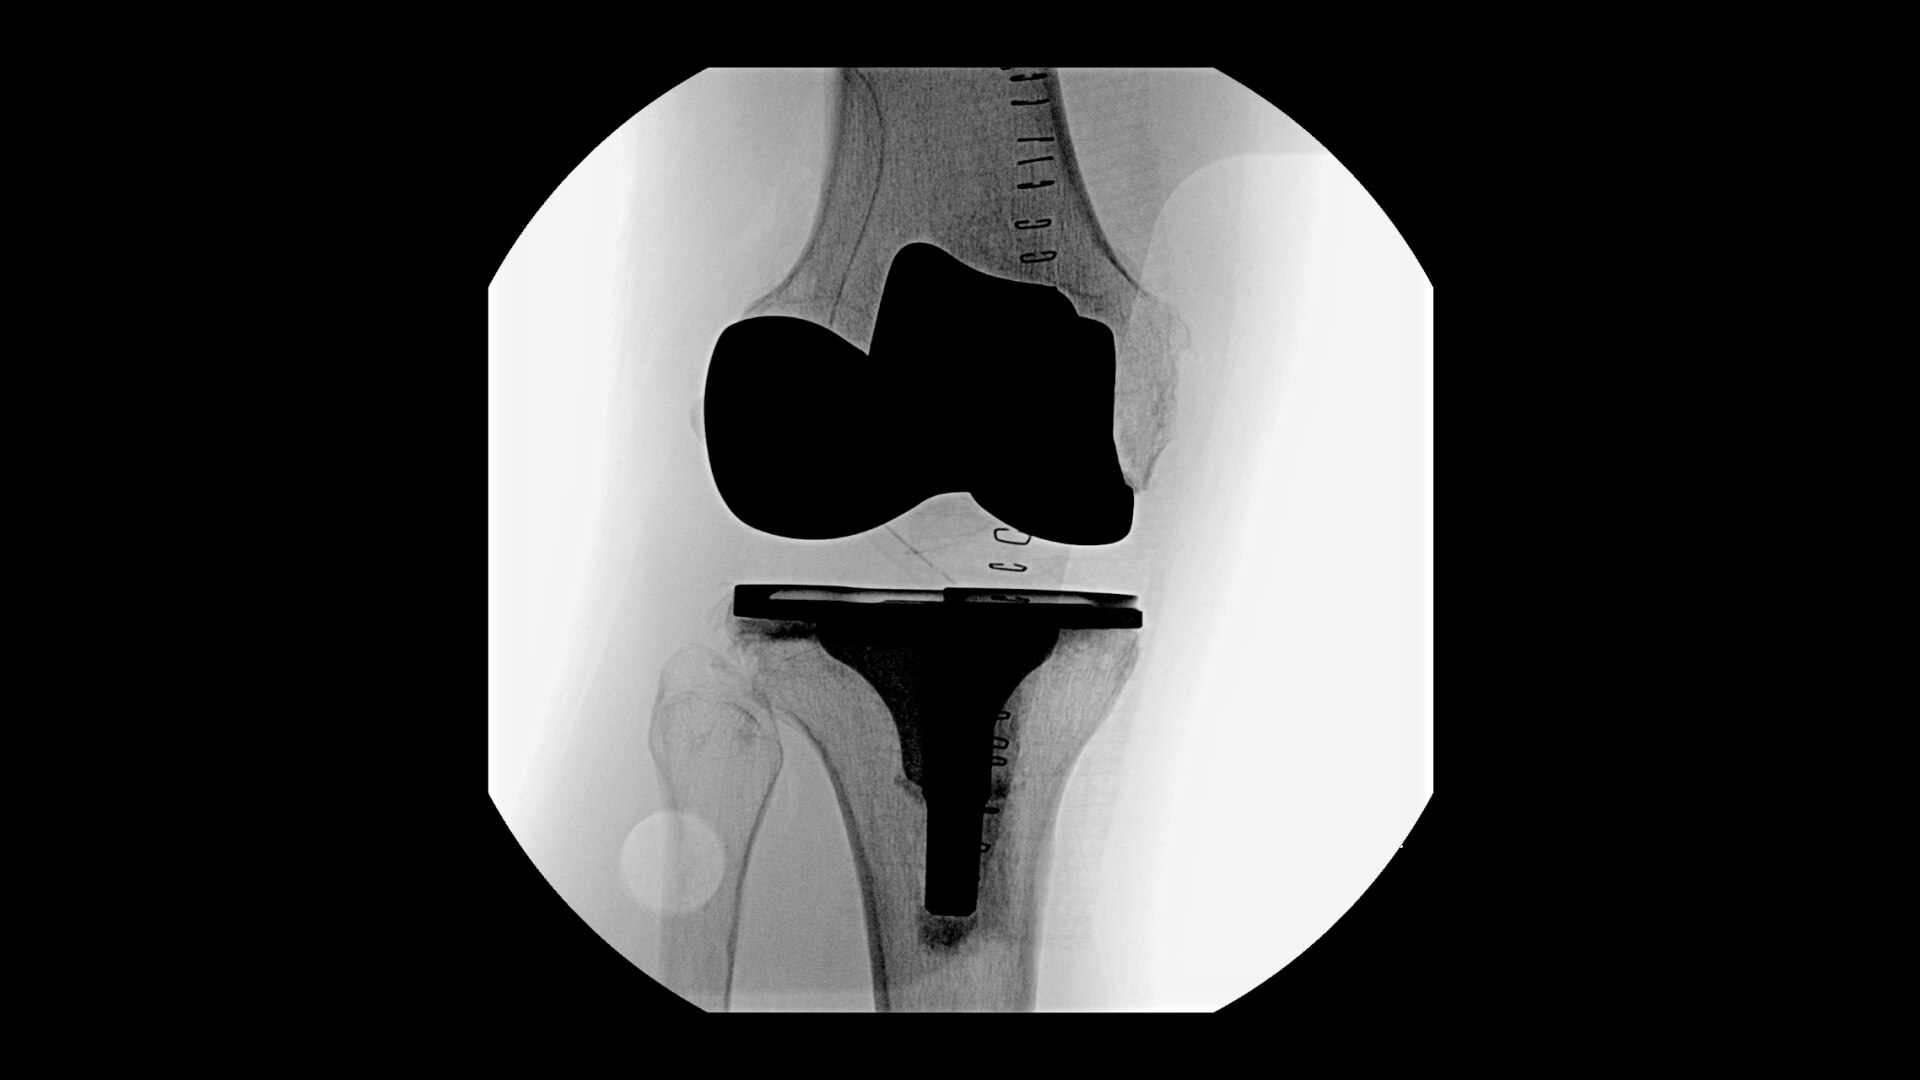

See precise anatomical detail of varying densities such as bone and soft tissue with a high dynamic range with the OEC Elite CFD with a flat detector, image processing advancements and 4K viewing display.

Complex orthopedic procedures require powerful imaging systems. OEC premium C-arms perform in a variety of procedures such as:

• Knee replacement